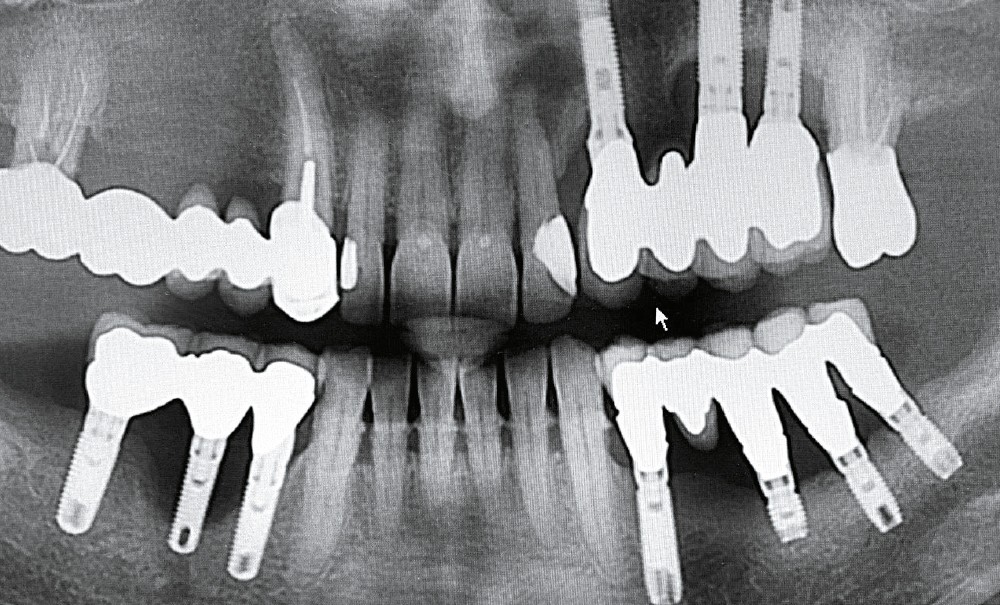

Je recherche des signes cliniques tels que la suppuration, facile à objectiver par simple pression digitale. Je sonde peu car la forme des implants, les profils concaves des piliers, les bombés proximaux rendent cet examen difficile et, finalement, assez peu fiable. Je réalise une radiographie panoramique annuelle associée à des rétro-alvéolaires dès qu’une image est insuffisante ou me paraît suspecte.